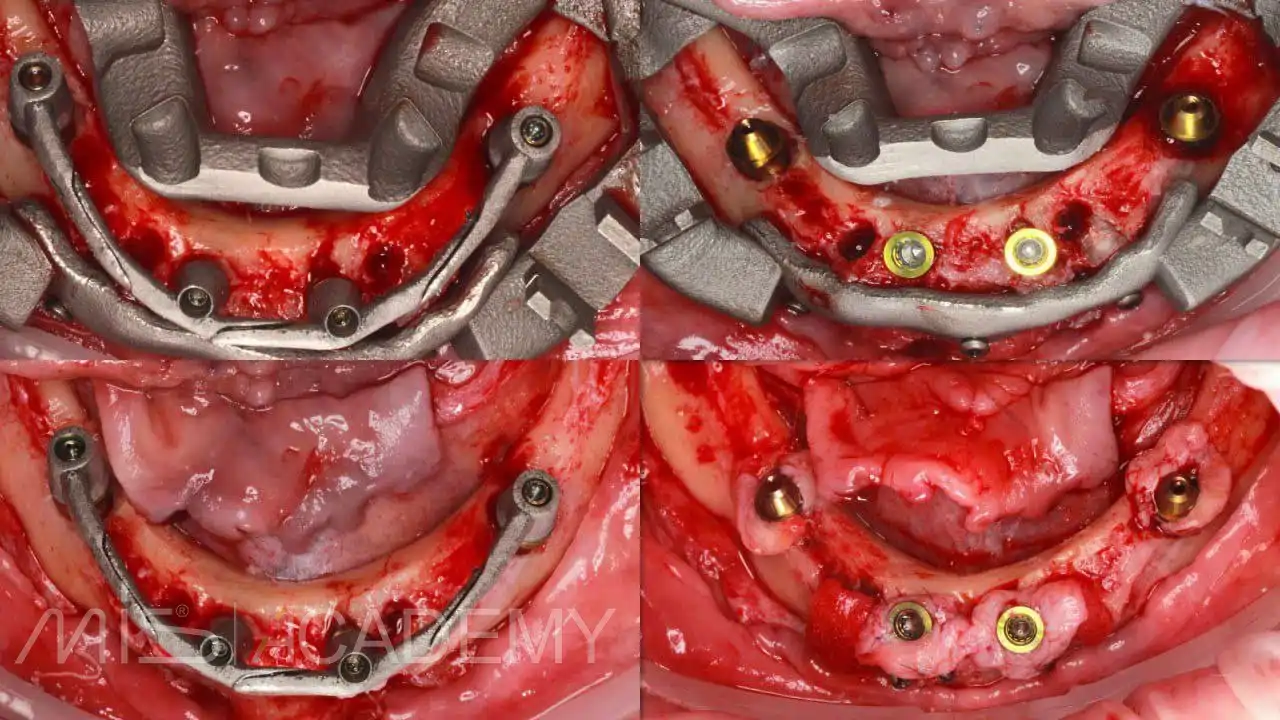

— Multifix на 4-х MIS C1.

— Коннекты во фронте.

— 30 градусов МЮ дистально.

— Мягкотканная пластика + B2S в критических зонах вестибулярно.

— Навигация полнопротокольная, разборная, накостная.

— Нагрузка немедленная, внутриротовая сварка.